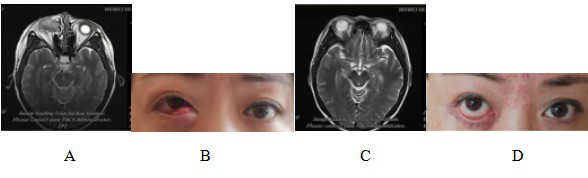

图 3 泪囊鳞癌患者CIRT治疗前后磁共振成像(MRI)及体征对比图

Figure 3 Comparison of magnetic resonance imaging (MRI) and physical signs in patients with dacryocystosquamous cell carcinoma before and after CIRT treatment

Note: Figure 3A: MRI examination before CIRT treatment showed that: the right lacrimal sac was occupied, the boundary between the eyeball, the medial rectus muscle and the inferior rectus muscle was not clear, the eyeball was compressed and displaced, and the right nasolacrimal duct was invaded. Figure 3B: Abnormal signs before CIRT treatment; Figure 3C: MRI examination after CIRT treatment showed that: the lesion disappeared, and the efficacy evaluation was CR; Figure 3D: Recovery of physical signs after CIRT treatment.

图6脉络膜恶性黑色素瘤患者CIRT治疗前后MRI对比

Figure 6 Comparison of MRI before and after CIRT treatment for malignant melanoma of choroid

Note: Figure 6A: MRI examination results before CIRT treatment showed: Abnormal signal nodules on the right side of the base of the eyeball. The red circle shows the extent of tumor invasion.

Figure 6B: MRI results after CIRT treatment showed: Abnormal signal nodules on the right lateral temporal side of the base of the eyeball, with little change compared with before.

Figure 6C: MRI examination 90 days after CIRT treatment showed that: the lesion disappeared and the efficacy was evaluated as CR.